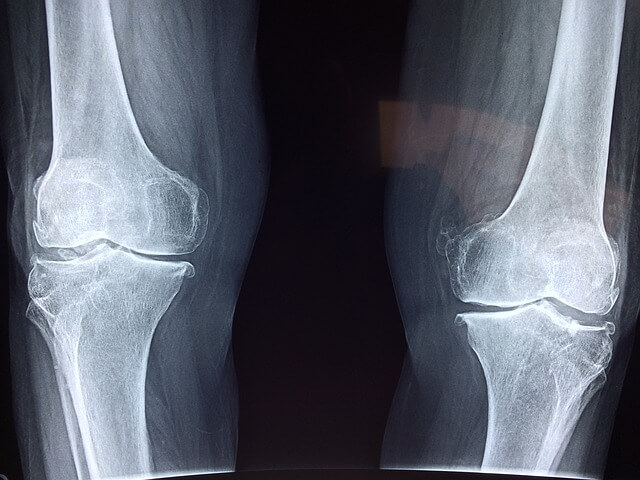

1. 관절 건강 증진: 콘드로이친은 연골의 구성 성분으로, 관절 강직과 손상을 막는 데 도움 됩니다. 또한 연골 조직의 천연 스펀지 역할을 해 원활한 관절 움직임에 기여하며 관절 내 충격 흡수능을 증진시킵니다.

2. 연골 손상 예방: 콘드로이친은 인체 내에서 연골의 탄력을 높이고 주기적인 새로운 세포 생성을 도와 손상된 연골을 회복시키며 추후 손상을 예방하는 데 도움이 됩니다.

3. 관절염 증상 완화: 콘드로이친이 관절 염증과 통증을 줄이는데 도움을 주며 특히 고관절염, 무릎관절염 등 관절염 환자에게 효과적입니다. 글루코사민과 함께 사용하면 더욱 효과적인 증상 완화가 기대됩니다.

4. 통증 감소: 콘드로이친 복용으로 인한 통증 완화 효과가 뚜렷한 것으로 알려져 있습니다. 수술 못지않은 효과를 거둔 예도 있습니다.

5. 관절 윤활제 생성 촉진: 콘드로이친은 인체에서 자연으로 생성되는 관절 윤활제의 생성을 촉진하며 연골과 뼈 마모를 줄이고 관절의 원활한 움직임을 지원합니다.

6. 연골 재생: 노화로 인한 연골 손상이 증가할 수 있으나 콘드로이친을 섭취해 나이가 들어도 연골의 손상을 줄이고 건강한 관절 상태를 유지할 수 있습니다.